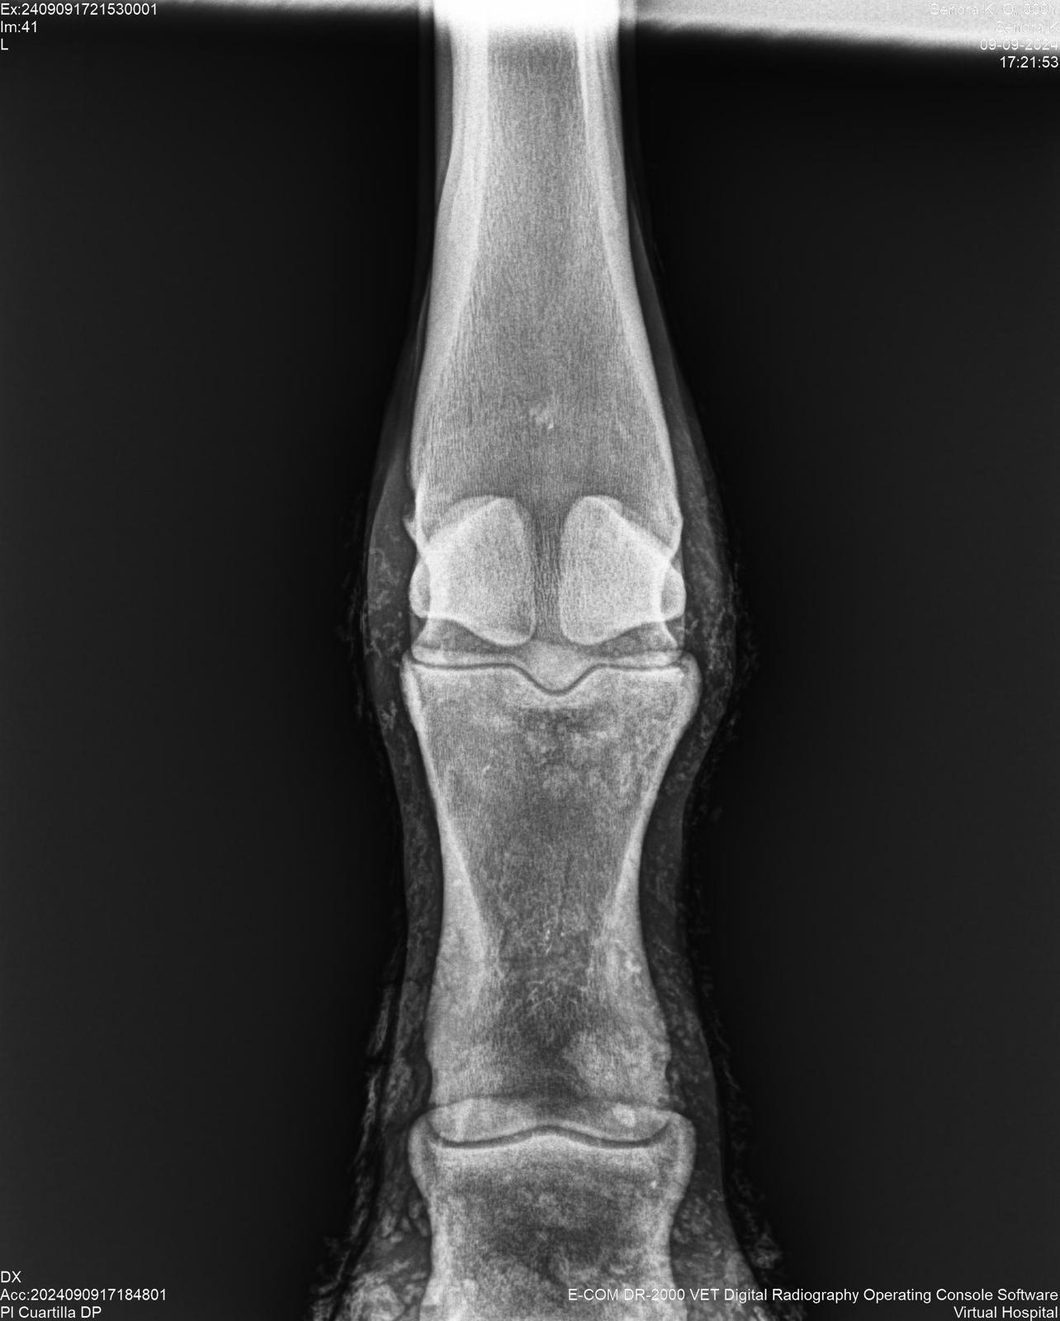

LOTE 44, SEÑORA K

Identificador: #291147-

Generacion 2022